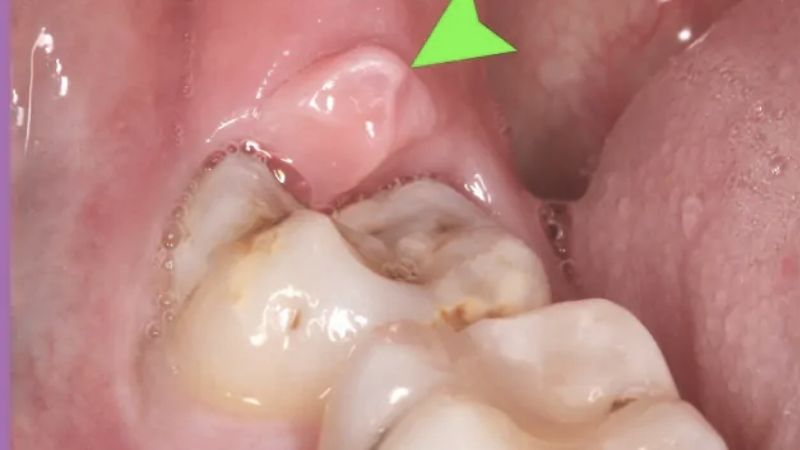

Răng khôn, còn gọi là răng số 8, là chiếc răng mọc ở cuối hàm, thường xuất hiện trong độ tuổi từ 17 đến 25. Do không có đủ không gian để mọc đúng vị trí hoặc mọc lệch, chúng thường gây ra các vấn đề như:

1. Tình trạng răng và vị trí mọc

Răng khôn mọc thẳng, đúng vị trí và không gây biến chứng sẽ có giá thấp hơn. Trong khi đó, răng mọc lệch, nằm sâu, hoặc gây viêm nhiễm sẽ cần kỹ thuật phức tạp hơn, dẫn đến chi phí cao hơn.